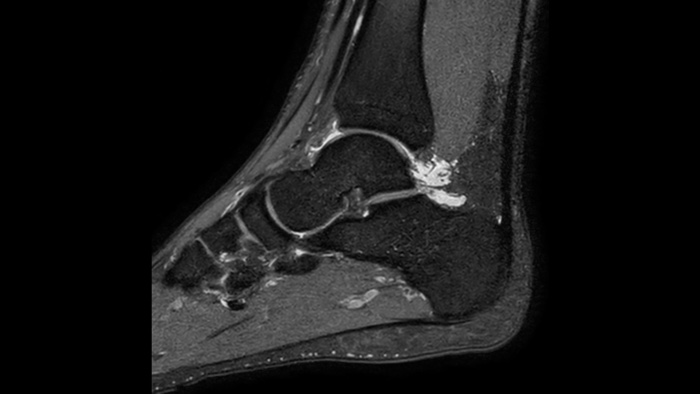

Imagen clínica del tobillo

Confianza diagnóstica

Ofrece una resolución espacial hasta un 60% más alta en el mismo tiempo de escaneo. 4